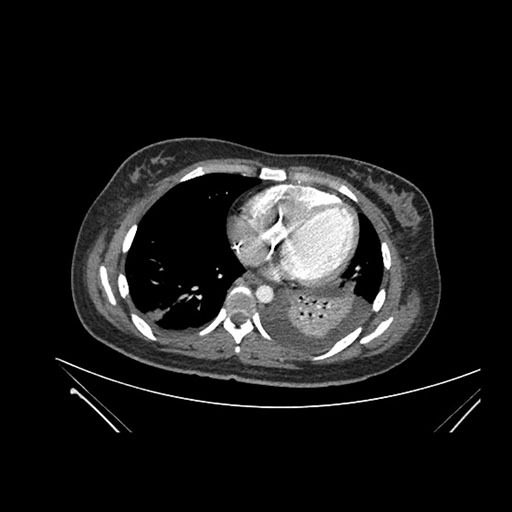

Imaging Analysis

Look through the patient's CT scan to identify any areas of concern for the necessary procedure.

Based on initial findings, which issue(s) would you be most concerned about?